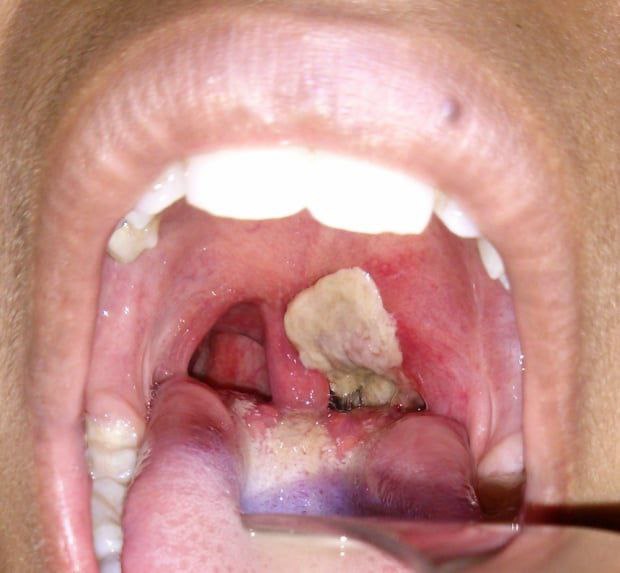

❓Difteriya qanday kasallik?Uning belgilari va asoratlari qanday? 📌Difteriya (yun. diptherien — parda, et), boʻgʻma — asosan hiqildoq, tomoq shilliq pardalarining yalligʻlanishi va aʼzolarning zararlanishi bilan kechadigan oʻtkir infeksion kasallik. 📌Difteriya kasalligining belgilari: 🔶Siydik chiqarishda og‘riq; 🔶Yiringli ajralmalar; 🔶Nafas olishning qiyinligi; 🔶Intensiv…